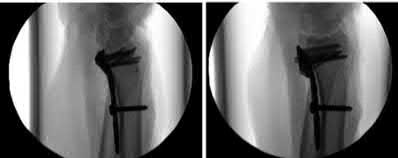

Question 19

A 28-year-old male sustains a closed comminuted tibial shaft fracture.

Two hours post-injury, he develops severe leg pain unyielding to narcotics. His blood pressure is 120/80 mmHg. Intracompartmental pressure monitoring is performed. Based on current guidelines, which measurement dictates an emergent 4-compartment fasciotomy?

Explanation

Acute compartment syndrome is classically defined by tissue hypoperfusion. The absolute compartment pressure is less reliable than the differential pressure (Delta P). A Delta P (Diastolic Blood Pressure minus Compartment Pressure) of less than 30 mmHg is an absolute indication for emergency fasciotomy, as capillary perfusion gradient is lost when tissue pressure approaches the diastolic pressure.